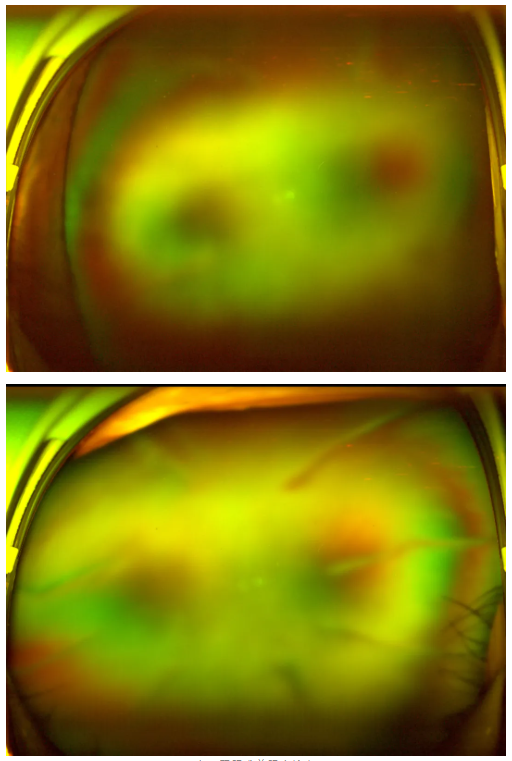

老王雙眼術(shù)前眼底檢查

“別灰心,好好配合治療,你還是有很大機會能恢復(fù)部分視力的。”王曉波主任的話像一顆定心丸,讓老王懸著的心得以放松。在醫(yī)生的指導(dǎo)下,老王先積極穩(wěn)定血糖,為后續(xù)治療打下堅實基礎(chǔ),隨后多次轉(zhuǎn)機重返廈門眼科中心辦理入院,準(zhǔn)備接受針對性治療。

王曉波主任告知老王:術(shù)后復(fù)查眼底顯示,其糖尿病視網(wǎng)膜病變并不嚴(yán)重,因此視力得以得到明顯改善與提升。當(dāng)初堅持治療、不輕言放棄,是非常正確的選擇!

糖尿病視網(wǎng)膜病變